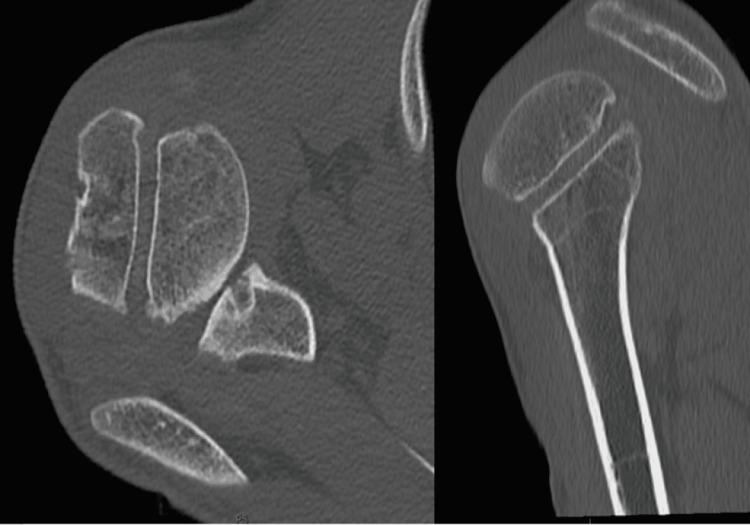

复杂的肩肱关节后向不稳病例管理

Complex Posterior Glenohumeral Instability Case Management.

A 21-year-old male patient suffering from insidious shoulder instability from neurogenic and structural attenuation of shoulder stabilizer, due to old minor cerebrovascular accident, presented with a two-year history of repetitive shoulder dislocation, operated by fixing the biceps tendon to its insertion on the superior labrum, correction of the glenoid version and reattaching the subscapular tendon along with a new technique for stabilization of the shoulder replicating the coracohumeral ligament with a ligament advanced reinforcement system (LARS) transplant. Following structured physical therapy, our patient returned to normal daily activities at 15 months.

摘要

一名21岁男性患者,因陈旧性轻度脑血管意外导致肩部稳定器神经源性和结构性减弱,出现隐匿性肩部不稳定,有两年反复肩关节脱位病史。手术方式为将肱二头肌肌腱固定于其在上盂唇的附着点,矫正肩胛盂形态,并重新附着肩胛下肌腱,同时采用一种新的肩部稳定技术,即使用韧带推进增强系统(LARS)移植来复制喙肱韧带。经过系统的物理治疗,该患者在15个月时恢复了正常日常活动。